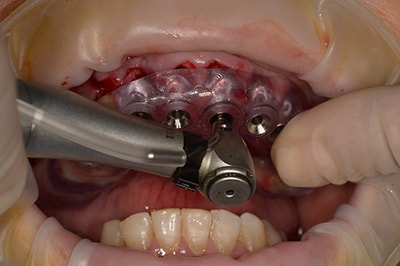

Chirurgie Guidée

L’implantologie moderne évolue vers un positionnement des implants dicté par la prothèse. Il permet et garantit un meilleur résultat esthétique, une meilleure distribution des forces et une hygiène facilitée. La combinaison de l’imagerie 3D et de logiciels de planification autorise des études préliminaires d’une grande finesse. On pourra ainsi visualiser la faisabilité prothétique d’un plan de traitement implantaire.

Au cabinet, pour les cas complexes, après réalisation d’une imagerie 3D (scanner ou cone beam), le cas sera étudié (avec un logiciel de planification), et une solution sera proposée. Dès validation, un guide chirurgical sera confectionné, dans l’absolu respect de la planification. Il permettra de positionner et placer chaque implant dans la position et l’axe pré-défini.

Plusieurs types de guides sont possibles. S’il reste des dents sur l’arcade, nous réaliserons un guide dento-porté (stable et précis). S’il ne reste aucune dent, nous devrons réaliser un guide ostéo-porté.

Ce type d’intervention permet au patient, de repartir le jour de l’intervention, avec une solution esthétique et fonctionnelle.